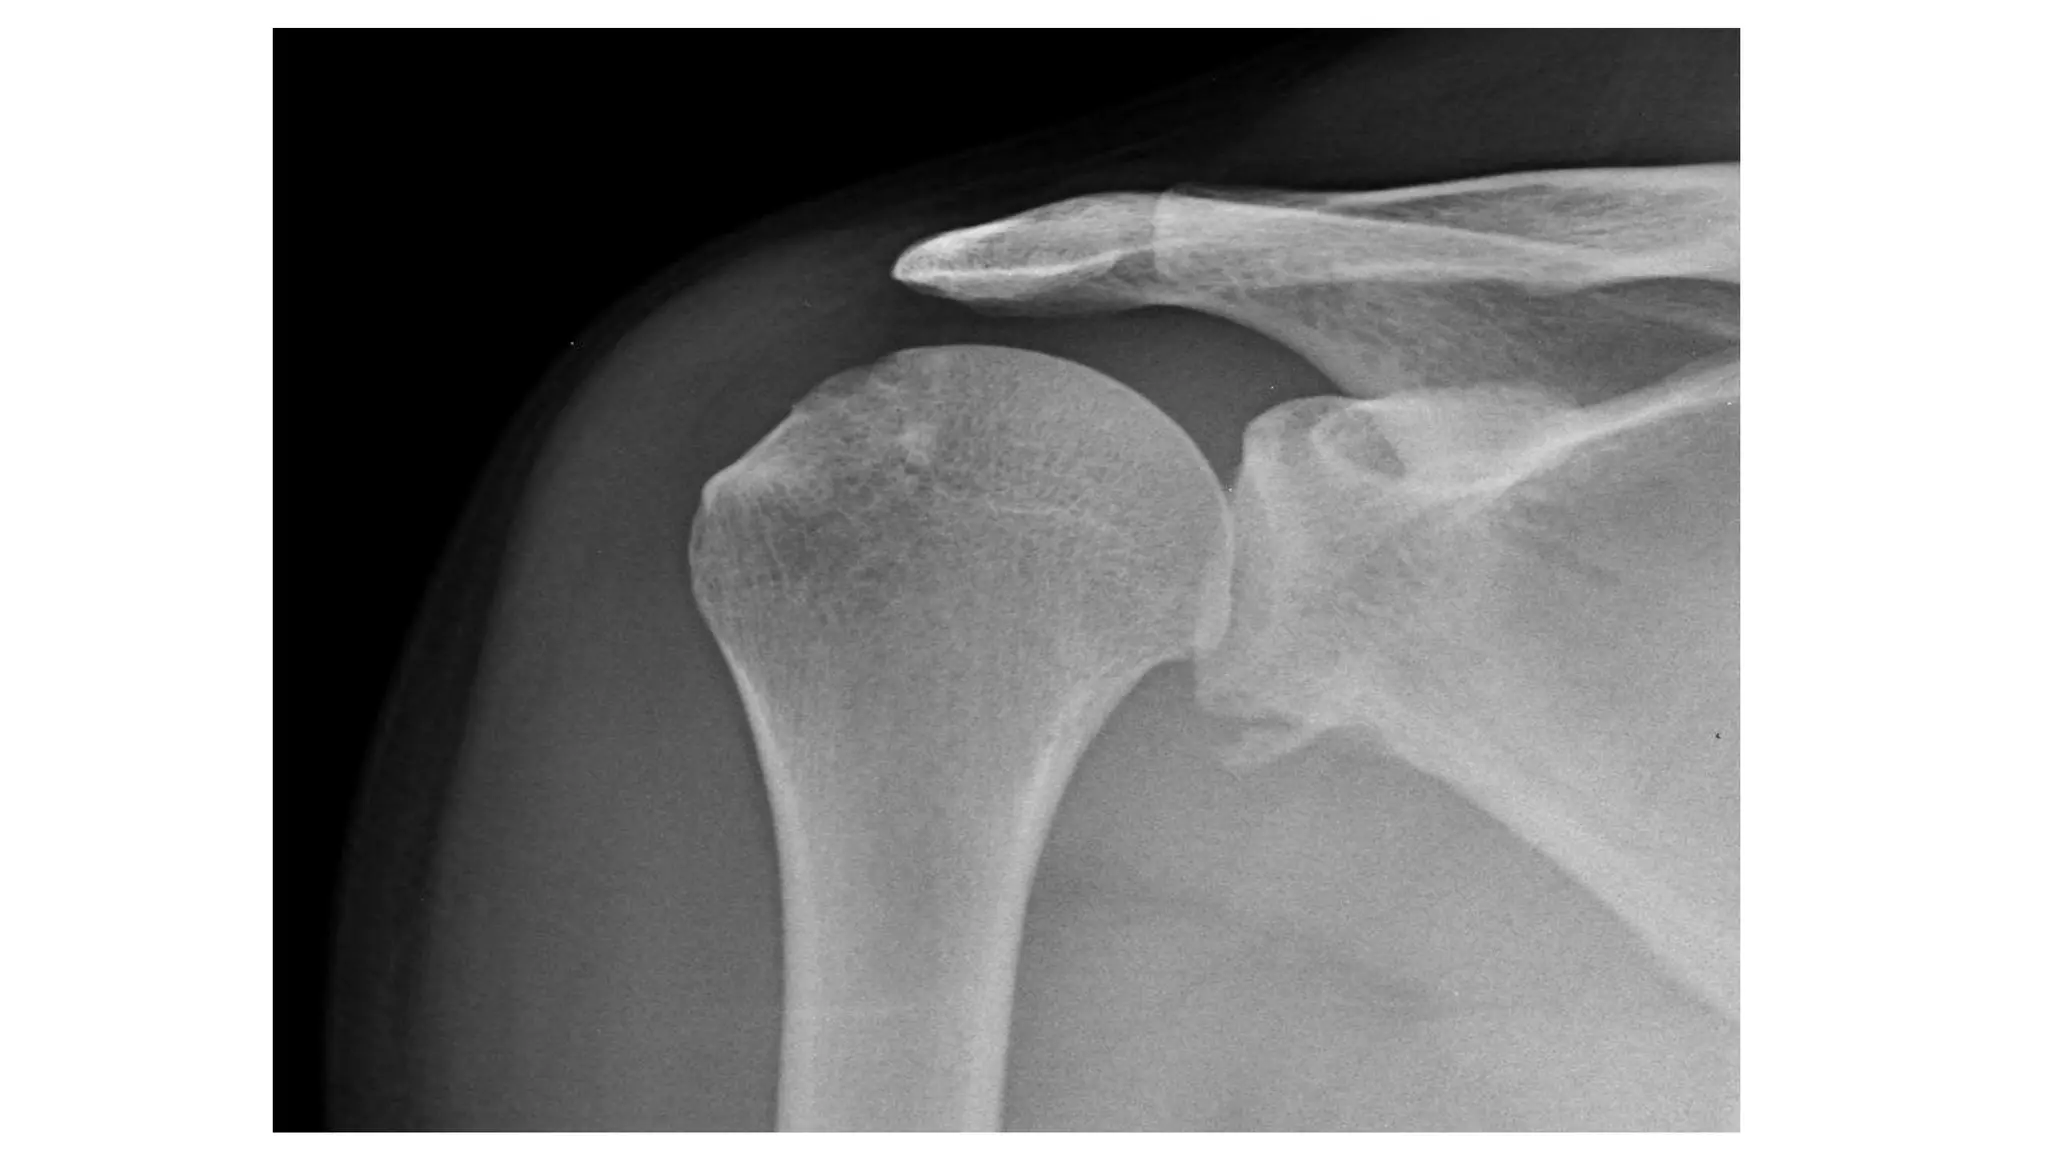

Imaging

Radiographs

• true AP

• scapular Y

• axillary

other helpful views

• West Point view :- shows glenoid bone loss

• Stryker view :- shows Hill-Sachs lesion

• CT scan

• helpful for evaluation of bony injuries

• MRI

• best for visualization of labral tear

• addition of intraarticular contrast

• increases sensitivity and specificity

True AP

Scapular Y view

Axillary view

West point view

Stryker view